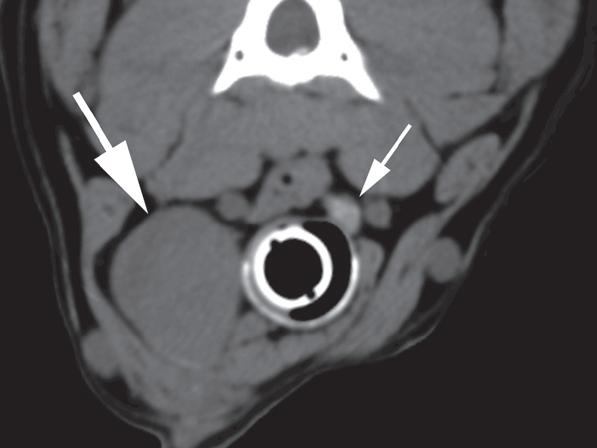

Badanie wykonano u 12-letniej, kastrowanej samicy labradora retrievera z wcześniej zdiagnozowanymi masami płucnymi i szyjnymi. W badaniu USG uwidoczniono kulisty, hipoechogeniczny guzek w obrębie prawego płata tarczycy (a). W TK masa jest nieznacznie hipodensyjna w obrazach bez wzmocnienia (b – strzałka). Lewy płat tarczycy ma prawidłową wielkość i jest hiperdensyjny (b – grot strzałki). Masa ulega umiarkowanemu wzmocnieniu po podaniu środka kontrastowego, jednak w mniejszym stopniu niż sąsiedni prawidłowy miąższ tarczycy (c – strzałka) i jej przeciwległy płat. W obrazach w rekonstrukcji grzbietowej w projekcji MIP po podaniu środka kontrastowego uwidoczniono przebieg obu tętnic szyjnych wspólnych dogrzbietowo względem płatów tarczycy (d – groty strzałek). Cieńszy przekrój MIP wykluczający tętnice szyjne ukazuje płaty tarczycy (e – strzałki) oraz lokalizację masy w obrębie prawego płata (e – grot strzałki). Biopsja wycinkowa wykazała raka tarczycy o utkaniu litym i pęcherzykowym z naciekaniem naczyń i torebki